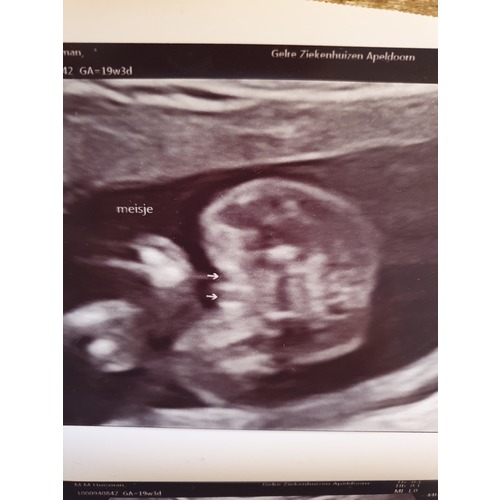

Als ik kijk naar mijn echo zie ik duidelijk het verschil

Oh grappig! Ook uit Apeldoorn :) ik zie nu eindelijk op jouw echo wat ik op mijne ook zie, van die uitstekende streepjes. Bij alle andere echo’s zag ik alleen maar “plat” tussen de benen. Vond mijne niet overtuigend eerst